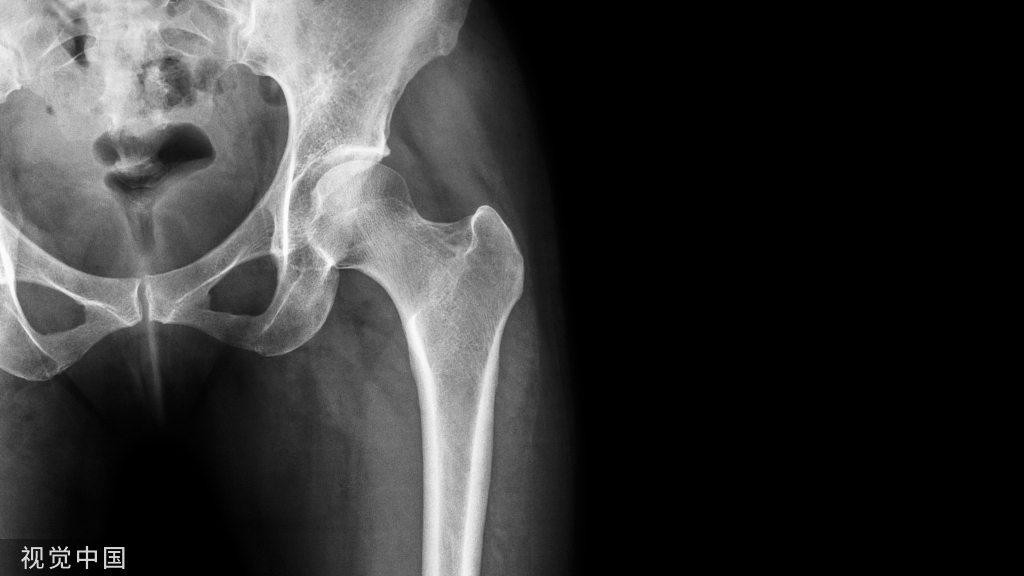

1883年,Carl Hueter首次报道髋关节直接前方入路(DAA)。DAA全髋关节置换术具有恢复更快、疼痛更轻的优势。但大多数研究报道,仰卧位直接前入路并发症相当高。仰卧位DAA和牵引床的使用可导致高达14.5%的并发症发生率,如股骨和转子骨折、股骨和髋臼穿孔、脱位、感染和伤口愈合问题。为了降低并发症,侧卧位DAA应用越来越多。但由于骨盆倾斜,侧卧位容易出现臼杯位置不当的问题。

• 骨性关节炎、股骨颈骨折初次髋关节置换;